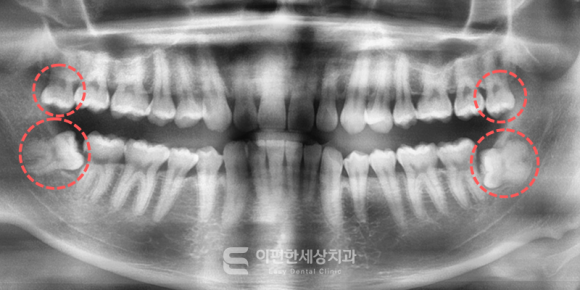

※이해를 돕기 위한 참고용 이미지입니다.

촬영일자 : 2024. 02. 16

검진을 통해 사랑니의 위치와 각도, 뿌리 형태,

신경과의 거리를 정확하게 파악할 수 있고

이러한 정보를 바탕으로 발치 계획을 세우기 때문에

예전보다 훨씬 안전하게 발치가 가능해졌죠.